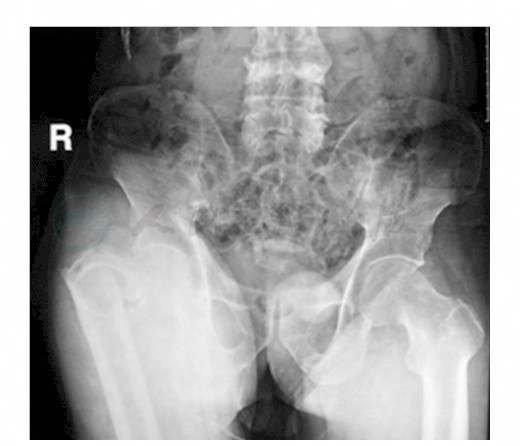

患者,男性,78岁。患者主因“外伤后右髋部疼痛,肿胀畸形,活动受限3天”入院。患者3天前行走时不慎摔倒,当即感左髋部疼痛,活动受限,无法行走。即来我院急诊,摄X线片示:右股骨转子间及转子下骨折。为进一步治疗收入院。入院查体:右髋关节肿胀,右侧股骨大转子压痛明显,髋关节活动受限。既往高血压病史16年,糖尿病病史5年,均药物控制稳定;10年前出现脑梗死,现残留右侧肢体部分功能障碍;慢性乙型病毒性肝炎8年,脾大,脾功能亢进;贫血;血小板减少性紫癜3年。结合查体及X线检查诊断:右股骨转子间及转子下骨折(图1)。

图1 骨盆正位X线片